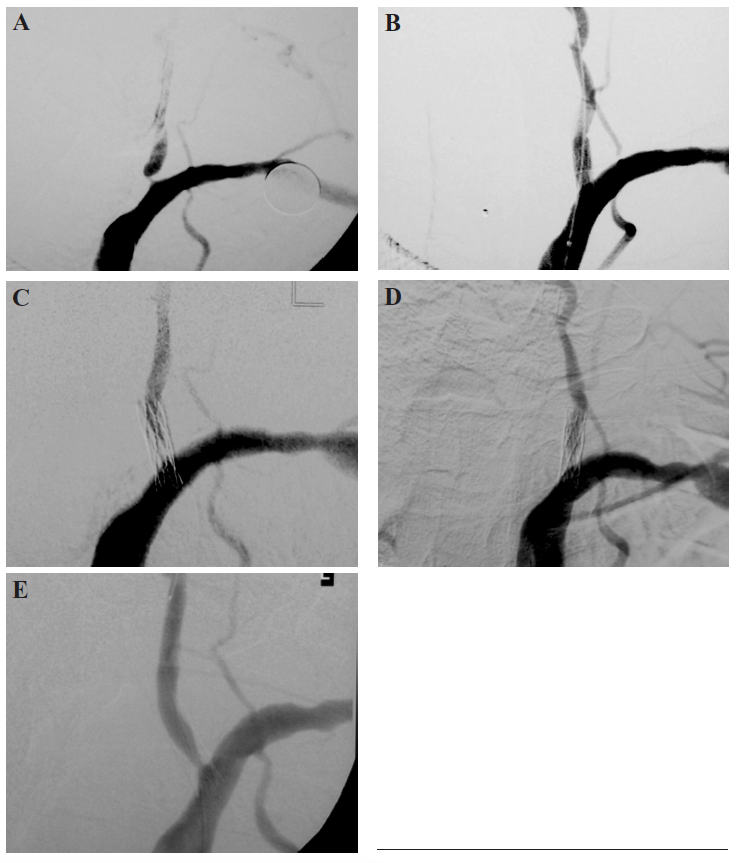

No procedural complications occurred at the time of initial stent deployment or angioplasty for restenosis. Restenosis was detected in 3 patients who had been treated with baremetal stents during the first year of initial follow up. The restenoses caused transient neurologic symptoms (TIAs) in 2 of those 3 patients. For example, our patient with bilateral carotid occlusions and right vertebral occlusion (Figure 1) reported an increase in his limb-shaking TIA symptoms, which are generally regarded as carotid territory symptoms around the time of in-stent restenosis. This implies that he was relying on posterior circulation collateral flow in the setting of bilateral internal carotid artery (ICA) occlusions.

After each of the two angioplasty treatments for his restenosis, these signs and symptoms subsided. Another patient developed classic visual migraine-like symptoms and drug-refractory hypertension with in-stent restenosis on two occasions. Both the visual migrainelike symptoms and the refractory hypertension resolved after each angioplasty. No recurrent stenosis or symptoms returned after a second angioplasty. A third patient was found to have an occlusion in the 3 mm bare-metal right vertebral artery stent despite prior diagnosis and treatment for restenosis with angioplasty at 7 months. This delayed stent occlusion was asymptomatic, as she had recanalized the previously occluded left vertebral artery. One patient died from pharyngeal cancer at 8 months, a second from lung cancer at 17 months. An exampleof a patient treated with a drug-eluting stent and follow up with angiography and CTA is shown in Figure 2.